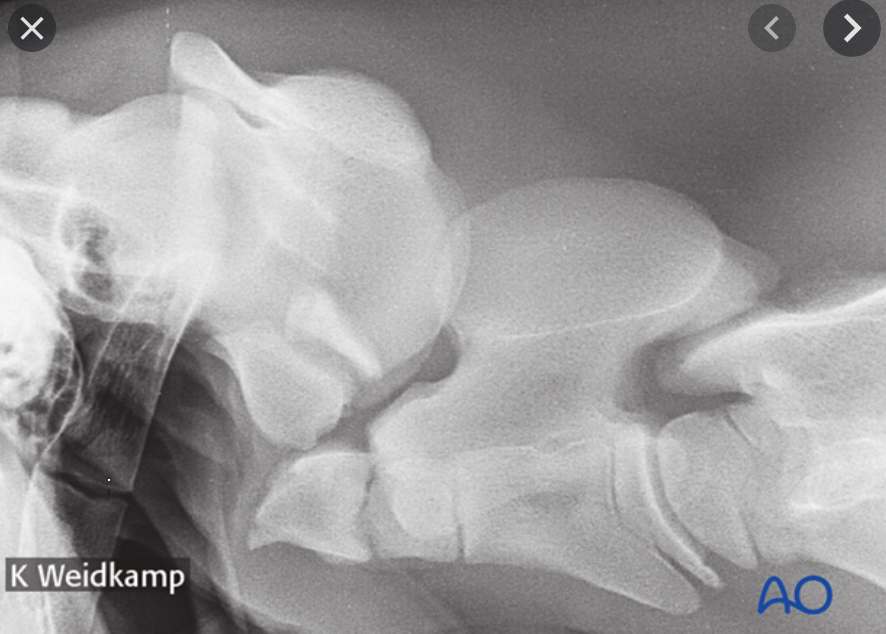

What is the diagnosis?

Complete ventral luxation of the dens

A - Atlas

B - Axis

a - odontoid process

b - Body of C2 - cranial

c - Vertebral body of C2, caudal

d - vertebral canal

e - caudal AP of C2

f - concavity of atlas where dens usually site

g - C2 DSP

Dens physis is closed so >8mo but cranial physis of C3 open so <2yrs